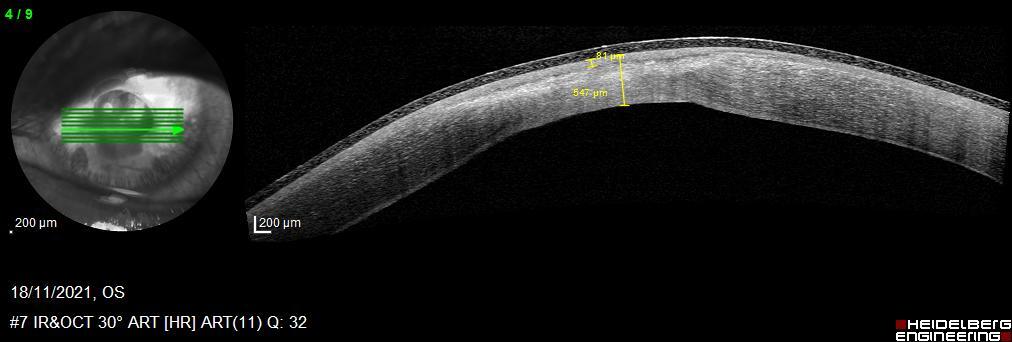

Initially, we filled the anterior chamber of the right eye with some air and patched the corneal defect with fibrin glue sealant (Tissucol ®). Then, we put a contact lens and added some topical antibiotics, and cycloplegic and artificial eye drops. Two days later, in the left eye, the corneal tissue was thinner and on the verge of perforation [figure 3]. Due to the urgency, surgical intervention was performed with an amniotic membrane graft. We used caruncular anesthesia. Two days later, there was no amniotic membrane graft. Rather, stromal thinning and descemetocele were found. We started to introduce amniotic membrane eye drops four times a day to our treatment for two months. We were not hopeful that this would work and the possibility of performing an evisceration was even raised. We followed up the evolution of the corneal thickness development with anterior segment optical coherence tomography [figure 4]. In two months the thickness went from 122 μm to 550 μm [figure 5].